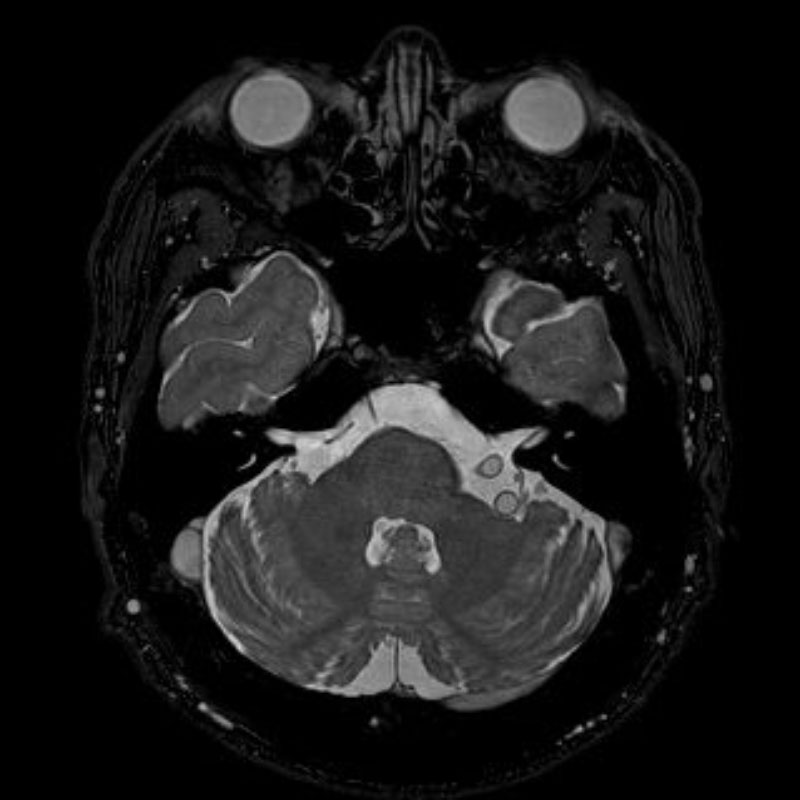

手術前

(MR1)

手術後

(CT)